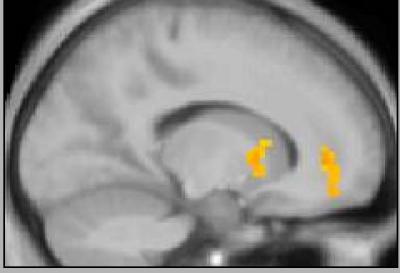

The brain processes "rewards"—things like food, money, and even pleasant music, which create positive responses in the body—in areas such as the ventromedial prefrontal cortex (VMPFC) and ventral striatum.

In a series of experiments, former Caltech postdoctoral scholar Elizabeth Tricomi (now an assistant professor of psychology at Rutgers University)—along with O'Doherty, Camerer, and Antonio Rangel, associate professor of economics at Caltech—watched how the VMPFC and ventral striatum reacted in 40 volunteers who were presented with a series of potential money-transfer scenarios while lying in an fMRI machine.

For instance, a participant might be told that he could be given $50 while another person could be given $20; in a second scenario, the student might have a potential gain of only $5 and the other person, $50. The fMRI images allowed the researchers to see how each volunteer's brain responded to each proposed money allocation.